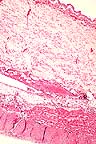

Severe submucosal edema in the rumen of a calf following chronic ingestion of an arsenic compound. (HE, 100X, 57K)

Epithelial necrosis, acute inflammation, and cleft formation in the rumen of a calf with chronic arsenic toxicosis. (HE, 200X, 54K)

Marked acute inflammation and hemorrhage in the rumen of a calf following chronic ingestion of an arsenic compound. (HE, 200X, 64K)

History: Several calves and cows were acutely ill. Several died in the last 4 months. This calf was alive when sent to the laboratory but died on the way. A bottle of MSMA herbicide (monosodium methanearsonate) was eventually found to have a pin-hole leak and had been dripping into a meal supplement in a storage shed.

Gross Pathology: The rumen had dark red blotches diffusely across the epithelial surface but the serosa was grossly normal. The abomasum contained milk curds and its mucosa was diffusely fiery red and a few Haemonchus sp. were present. The reticulum and omasum were grossly normal. The intestine and colon contained brown watery material and their mucosae were dull brown with a red tinge.

Laboratory Results: Rumenal contents were negative for arsenic. The liver was positive for arsenic at 1.92 ppm.

Contributor's Diagnosis and Comments: Superficially necrotizing subacute rumenitis (and omasitis) due to arsenic toxicity.

Whole blood from another sick cow had elevated arsenic at 0.14 ppm. Normal bovine liver arsenic levels are 0.004-0.4 ppm. High levels are 1.0-5.0 ppm and acute toxic levels are 2.0-15 ppm. Normal blood arsenic is 0.03-0.05 ppm and acute toxicity occurs from 0.17-6.7 ppm. Arsenic is rapidly cleared from the body (half-life 1.5 days). It is directly corrosive to the GI tract but also inactivates the sulfhydryl groups of oxidative enzymes within capillary endothelial cells; the liver, kidney and intestine are most sensitive. Capillaries become more permeable and the muscle layer of small arteries relaxes. The GI mucosa may slough away from underlying edema. In this calf, the abomasum and intestine were normal except for congestion and the other organs were normal microscopically. Fungal stains on the rumen and omasum were negative. The omasal lesions (not submitted on most slides) were much milder and more multifocal than those in the rumen.

AFIP Diagnosis: Rumen: Rumenitis, necrotizing, acute, diffuse, severe, with hemorrhage, edema, and focal arteritis, mixed breed, bovine.

Conference Note: Animals may be poisoned with arsenic through ingestion or percutaneous absorption. The most common sources of arsenic are insecticides and herbicides containing sodium arsenite, lead arsenate, or arsenic pentoxide. Poisoning occurs when animals gain access to recently sprayed pastures. Ore deposits frequently contain high levels of arsenic and poisoning may occur when pasture and drinking water are contaminated by exhaust from smelters. Other sources include wood preservatives and injectable preparations to control blood parasites.

In domestic animals, arsenic does not stay in the tissues very long. It is partially methylated in the liver and kidney and is rapidly excreted in urine, feces, bile, milk, saliva, and sweat. Arsenic may cross the placental and blood-brain barriers in small amounts. The milk from poisoned cows is toxic for humans and calves, but meat is considered safe for consumption.

The organs most susceptible to inorganic arsenic toxicity are the brain, lungs, liver, kidney, and alimentary mucosa. The lesions produced by acute poisoning can largely be explained on the basis of vascular injury. The lesions most commonly observed are severe congestion, edema, hemorrhage and vascular necrosis. Lesions in the stomach and intestines usually include intense congestion with edema, hemorrhage, and ulceration. Brain lesions usually include moderate, diffuse cerebral edema and petechiation. A peripheral neuropathy has been described. Chronic arsenic poisoning usually has the same anatomic distribution of lesions as acute poisoning. The application of arsenicals to the skin may result in a chronic dermatitis or, if absorption is rapid, systemic toxicity. The dermatitis is characterized by intense erythema, necrosis, and sloughing.